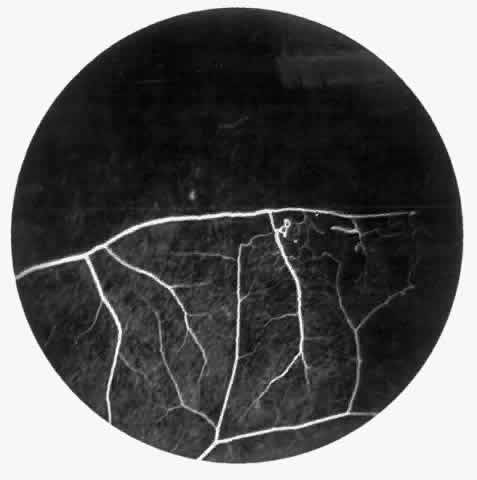

STAGE I: PERIPHERAL ARTERIOLAR OCCLUSIONS. This stage may be further subdivided into three grades: grade I, narrowing of the peripheral arterioles with tortuosity and abnormal looping of the peripheral venules; grade II, tortuosity, dilation, and microaneurysmal formation in the capillary network; and grade III, occlusion of the peripheral capillaries and arterioles.83

The occluded arterioles may be invisible or may have a “silver-wire” or chalk-white appearance, as first described by Goodman and colleagues39 (Fig. 21). Fluorescein angiography may demonstrate an abrupt complete occlusion at the interface between peripheral nonperfused and posterior perfused retina. Frequently, this occlusion will take place just distal to a branching vessel, giving the appearance of a freshly pruned rose bush. The nonperfused anterior peripheral retina will have a grayish brown appearance and on fluorescein angiography will appear blurred without clearly defined fundus markings.

Fig. 21. A. Photograph of the peripheral retinal vasculature shows sheathed vessels and absence of peripheral vascular perfusion. B. Fluorescein angiogram shows area of nonperfusion representing stage I sickle cell retinopathy. White arrow points to corresponding vascular bifurcation in A and B.